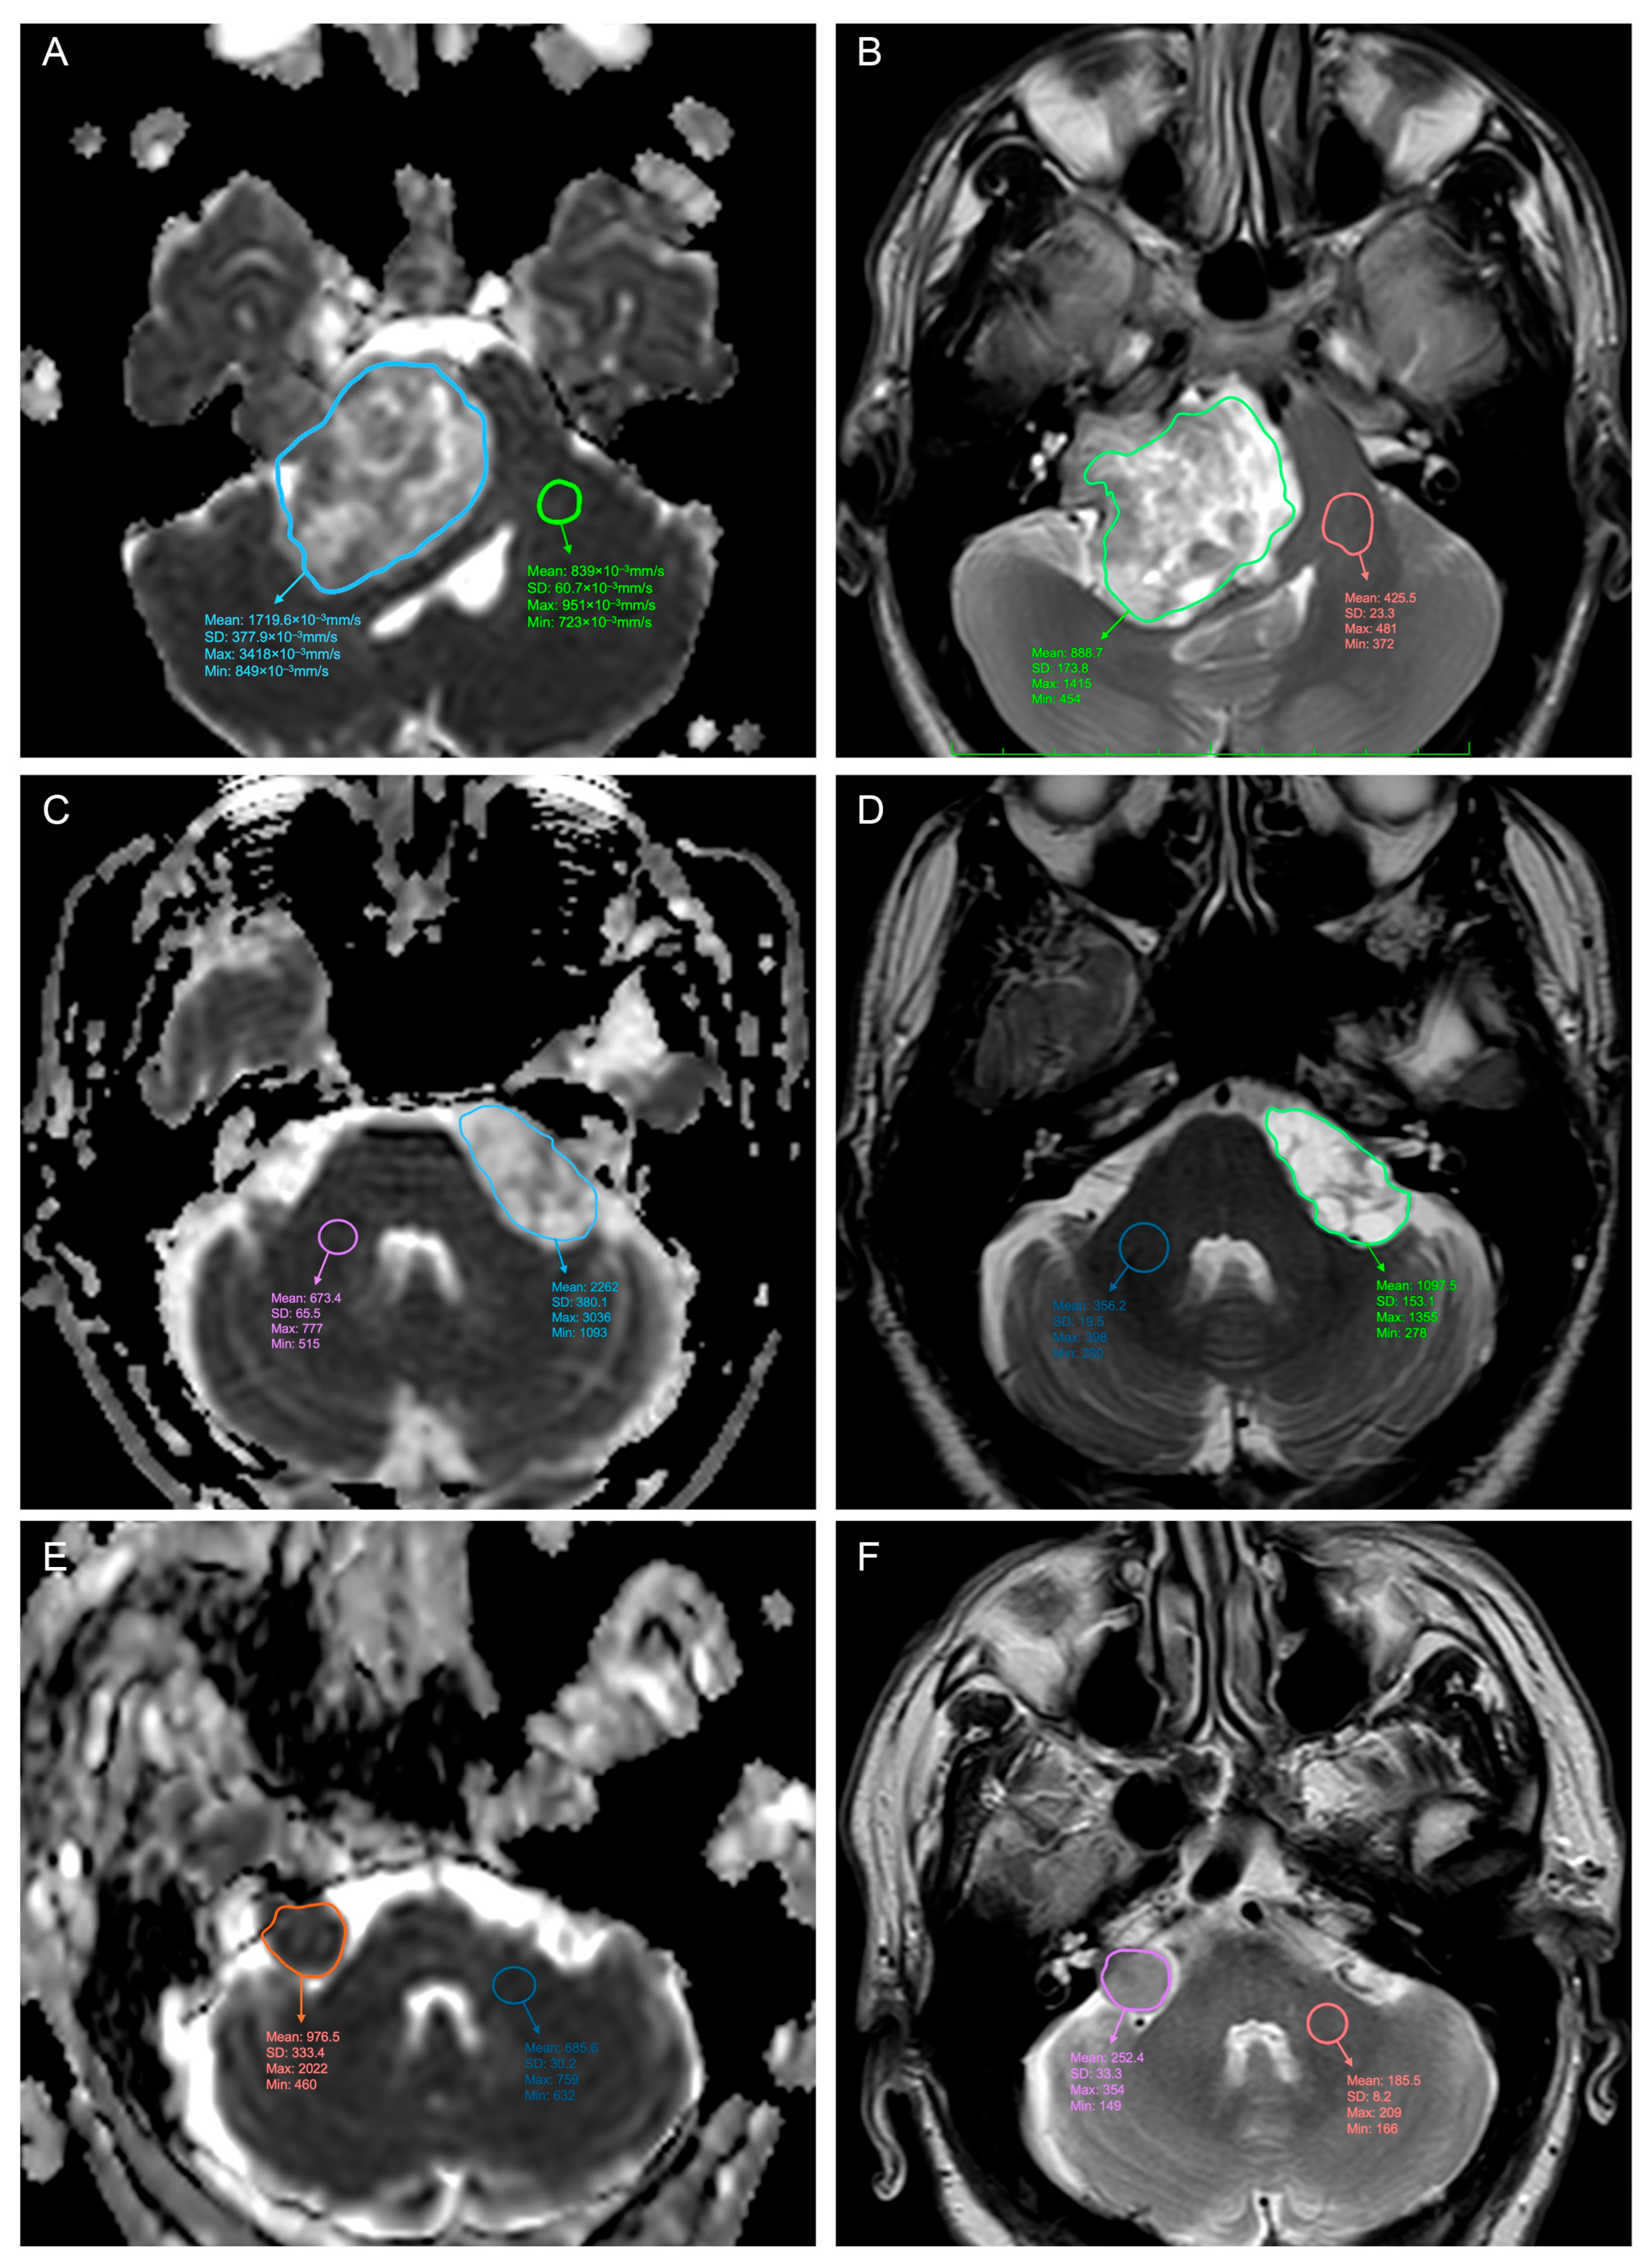

2. Materials and Methods

3. Results

3.1. Predicting the Consistency